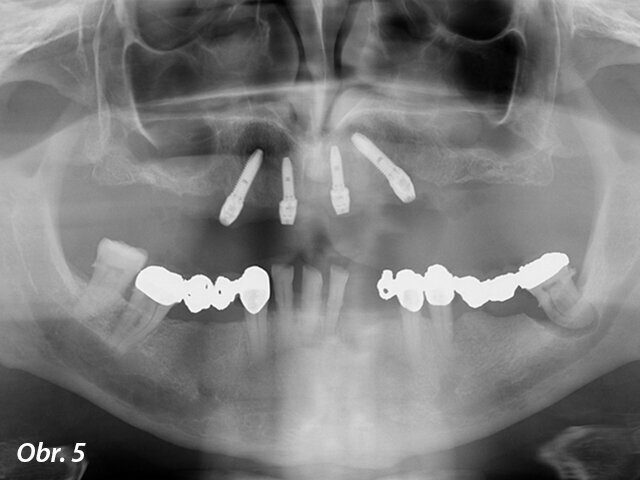

Ošetření každého případu „All-on-4“ začíná pořízením fotografií pacienta (obr. 3, 4) a naplánováním definitivní náhrady. V této fázi jsme velmi intenzivně diskutovali s pacientem, abychom zjistili, jaké problémy dříve měl a co očekává v budoucnu od nové náhrady. Následně jsme zhotovili otisky počáteční situace, zachytili ji pomocí obličejového oblouku a skusových registrátů a zaznamenali průběh okluze. Také jsme pořídili digitální panoramatické snímky a CBCT skeny, abychom naplánovali chirurgické a protetické kroky případu (obr. 5).